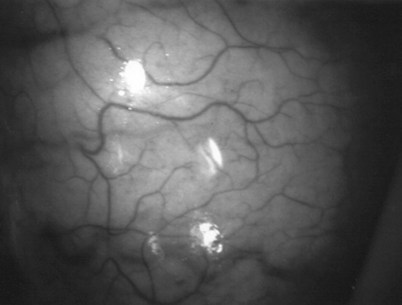

An assistant stretches the scrotal skin tightly over the anterior surface of the testis and confirms that the epididymis is posterior. Bilateral 1-cm transverse scrotal incisions provide good exposure with a minimum of scrotal bleeding (Fig. 22–1). Alternatively, a single vertical incision in the median raphe may be employed. The incision is carried through the skin and dartos muscle, and the tunica vaginalis is opened. If the anatomy is distorted from previous surgery, the epididymis cannot be clearly palpated posteriorly. If the tunica albuginea cannot be clearly identified, the incision should be enlarged and the testis delivered. The edges of the tunica vaginalis are held open with hemostats and any bleeding vessels are cauterized. Use of loupes or, better yet, the operating microscope allows ready identification of a spot on the tunica albuginea relatively free of visible surface vessels. The wound should be dry before incising the tunica albuginea to prevent saturation of the biopsy with blood. A 3- to 4-mm incision is made in the tunica albuginea with a 15-degree microknife (Fig. 22–2A). Small crossing vessels are cauterized with bipolar cautery and divided before excising a pea-sized sample of seminiferous tubules with razor-sharp iris scissors (Fig. 22–2B). When handling testis biopsy material for permanent fixation, avoid tissue handling in any way (including with forceps) because this may traumatize and distort the testicular architecture. The specimen is then deposited directly into Bouin, Zenker, or collidine-buffered glutaraldehyde solution. Formalin fixation results in distortion of testicular histology and should not be used for testis biopsy. A touch-prep is made by blotting the cut surface of the testis several times with a glass slide (Fig. 22–2C) and adding a drop of saline, lactated Ringer, or human tubal fluid with IVF medium and a cover slip. Examination under high power using a light microscope with or without phase contrast will reveal the presence of sperm with tails and allow assessment of motility (Fig. 22-2D). If no sperm are found in the touch prep, a second specimen may be cut for a wet squash prep. In this case the specimen is placed on a slide, a drop of saline is added, and the specimen is crushed under a coverslip (Jow et al, 1993). If no sperm are found, the tunica is closed with two to three interrupted sutures of 5-0 Vicryl (Fig. 22-2E) and another area is biopsied through the same skin incision. As described later in this chapter, use of an operating microscope providing 10× to 25× magnification may allow selective biopsy of larger seminiferous tubules more likely to contain sperm (Schlegel, 1999). If sperm are identified, the slide and additional tissue removed are sent for cryopreservation in the andrology laboratory. The location of the biopsy site where sperm were found is noted, and the tunica albuginea is closed with two to three interrupted sutures of 6-0 nylon. This assists identification of sites of spermatogenesis for future testicular sperm extraction for IVF/ICSI.

Figure 22–2 A, A 3- to 4-mm incision is made in the tunica albuginea with a 15-degree ultrasharp microknife. B, Small crossing vessels are cauterized with bipolar cautery, and a pea-sized sample of seminiferous tubules are taken with a no-touch technique. C, A touch-prep is made by blotting the cut surface of the testis several times with a glass slide. D, Examination under high power using a light microscope will reveal the presence of sperm and allow assessment of motility. E, The biopsy site is closed with two to three interrupted sutures of 6-0 nylon.